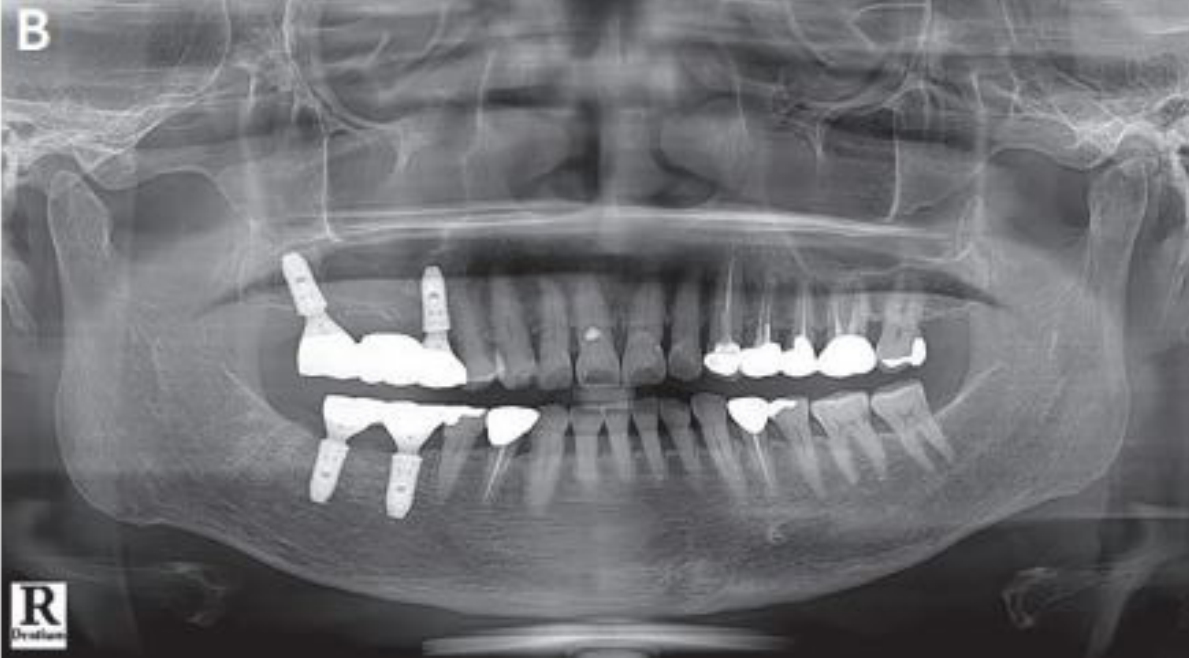

최근 digital techniology 의해 임플란트 보철물의 제작이 점점 증가되고 있지만 아직도 대부분의 임플란트 보철물은 인상채득에 의해서 모형위의 제작이 많은 것이 현실이다. 또한 최근 심미적이고 치주적인 관점에서 기성 abutment 에 비해 custom abutment가 많이 이용되고 있는 현실이다. 여기에서는 custom abutment를 위한 Fixture level 인상 채득 후 완성된 보철물의 장착을 위한 술식을 설명하고자 한다. 완성된 임플란트 보철물은 custom abutment를 이용하는 경우에, Abutment location Jig를 이용하여 구강 내에 Abutment를 장착한 후 보철물을 Bite stick을 이용해서 완전하게 seating시킨 후에 우선 인접치아와의 접촉정도 (자연치아 crown일 때보다 약간 tight한 것이 좋음)를 확인한 후 그리고 방사선 사진에서 fixture에 abutment가 잘 맞게 끼워졌는지 그리고 abutment와 crown간의 적합상태를 확인해야 한다(그림 15). 그 이후 교합관계를 확인 후 필 요하면 교합조정을 해야한다.